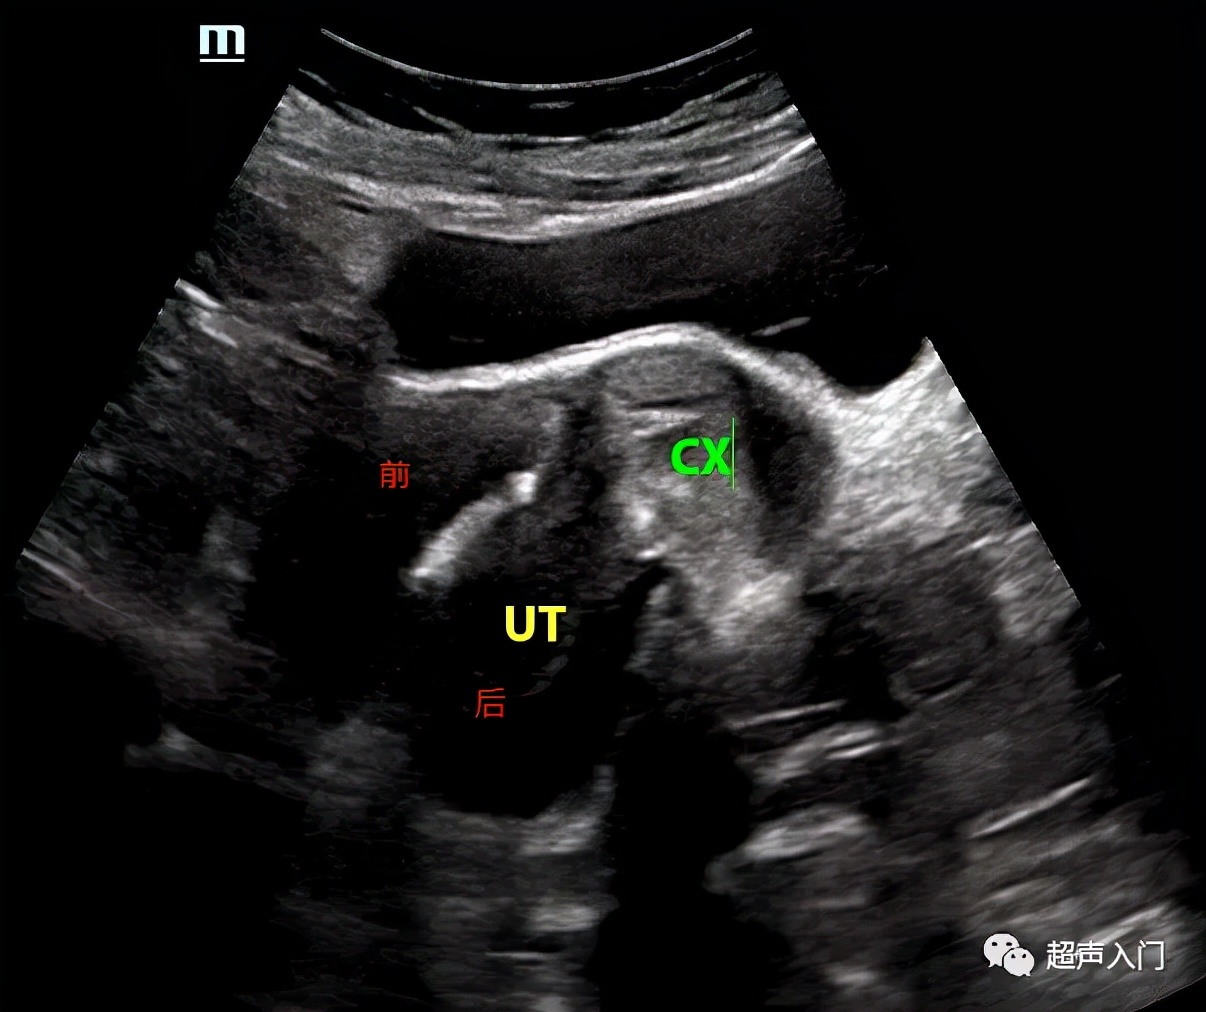

经阴道超声又如何分前后壁呢?

其实是一样的分发,离腹壁近的是前壁,如离背侧近的是后壁,只不过在阴道超声很多小伙伴不知道如何分前后左右了!

当经阴道超声矢状切子宫时,对应的图像就是下图这样的。

实际设备上的成像

当然,有的老师喜欢用反转后的图像,这个根据个人操作习惯来决定。但不管如何反转,始终是靠近腹侧的是前壁,靠近背侧的是后壁。